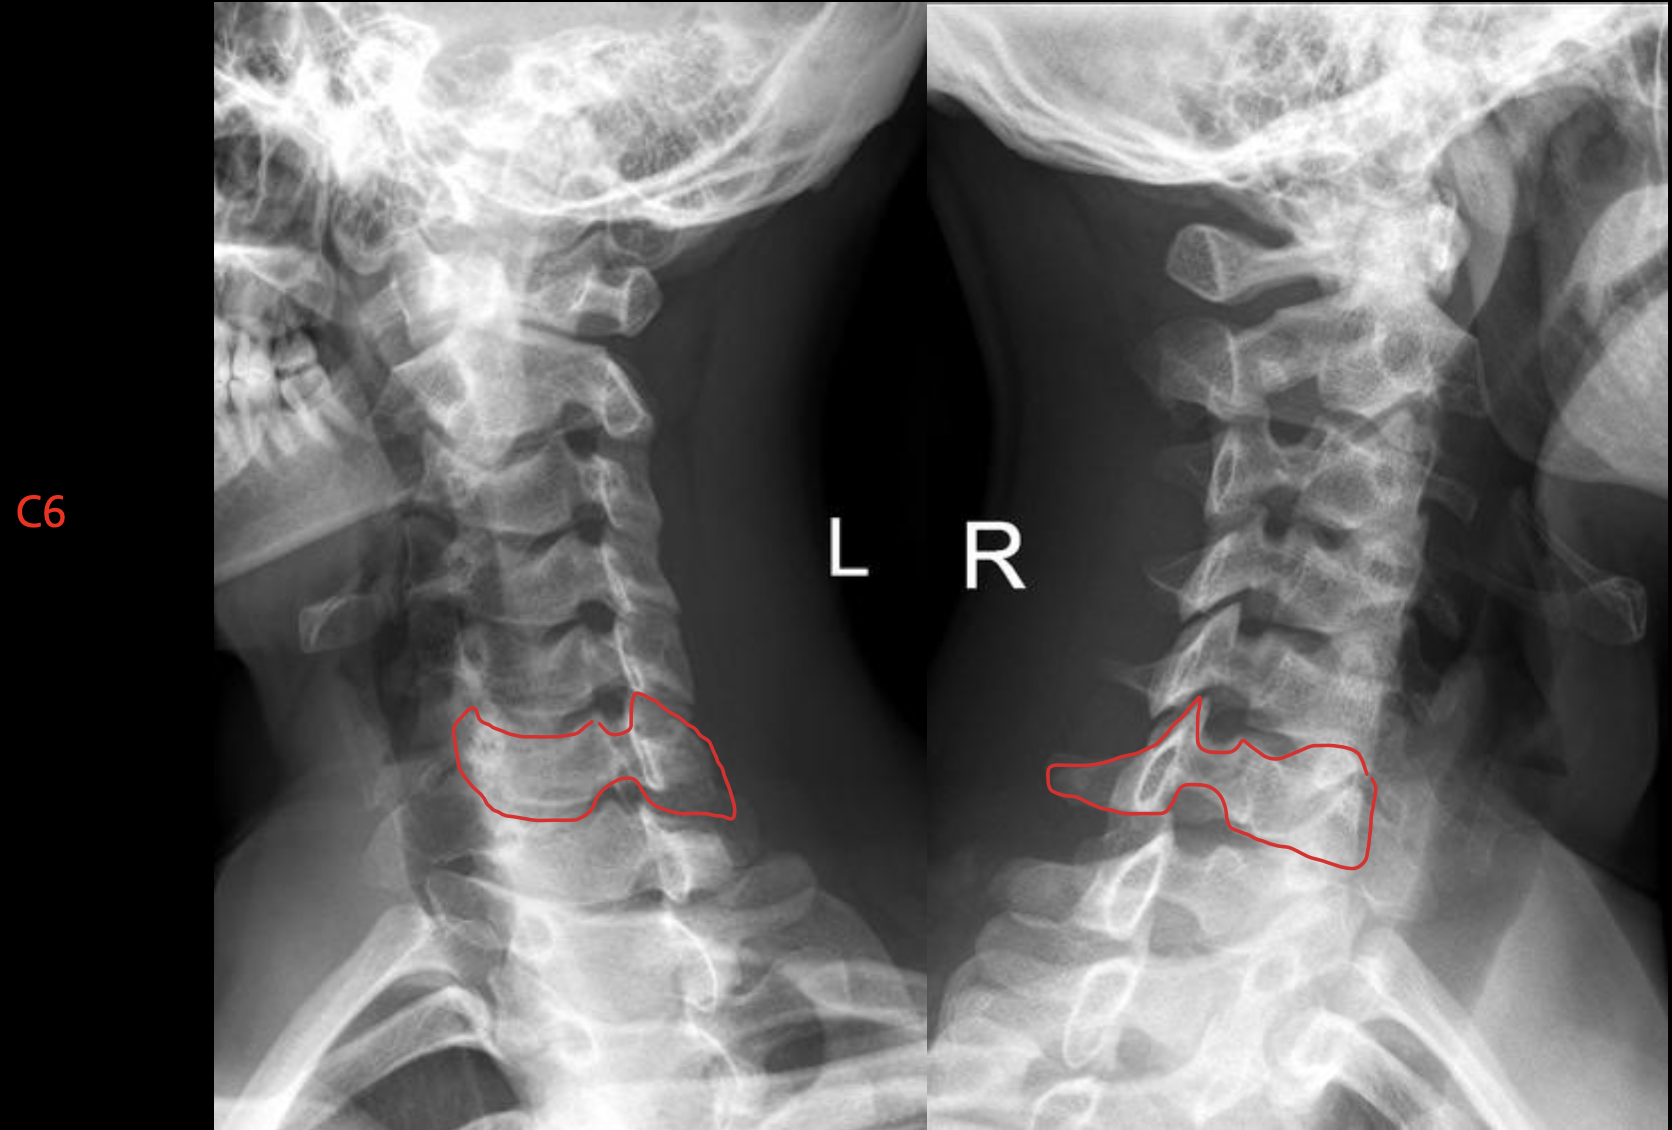

c6